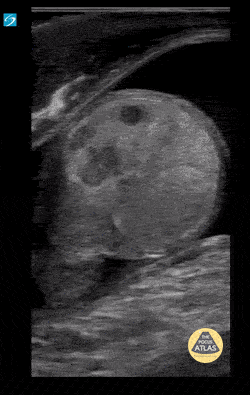

2 yo male with testicular torsion presenting at 48 hrs. Note the twisted spermatic cord, change of echogenicity of testicle and reactive hydrocele. Contributor: Paul Khalil, MD Nicklaus Children's Hospital @khalil3paul